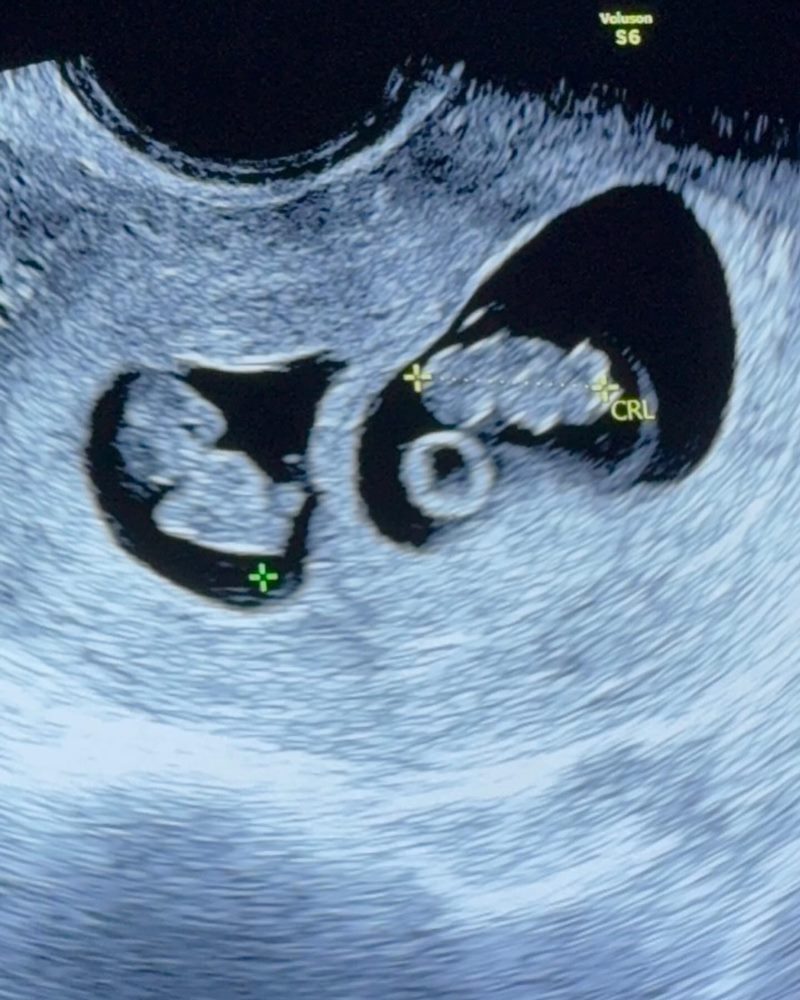

โดย คุณออย นันทิสา ได้โพสต์ภาพโชว์หน้าท้องของว่าที่คุณแม่ โดยมีมือของสามี คุณต๊อบ อัยยวัฒน์ สัมผัสอยู่ใกล้ ๆ กับรูปอัลตราซาวด์ลูกแฝดในครรภ์ พร้อมข้อความว่า "Twice the love, 2 lil dragons, 2 lil half of me & half of you #twinpregnancy"